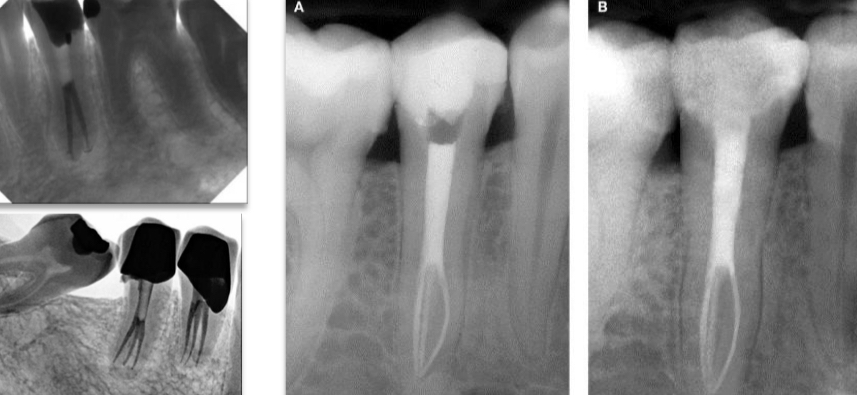

What are the 6 anomalies in maxillary 1st molar?

Single root and canal

2 distal canals

2 palatal roots

Variations in anatomy

3 MB canals

8 canals

What are common anomalies in maxillary 2nd molar?

1 canals

Pulp stones in pulp chamber

5 roots and canals

What is an anomaly in mandibular 1st molar?

3 roots- extra one called radix entomolaris

What is an anomaly in mandibular 2nd molar?

3rd root

1 conical root with c shaped canal